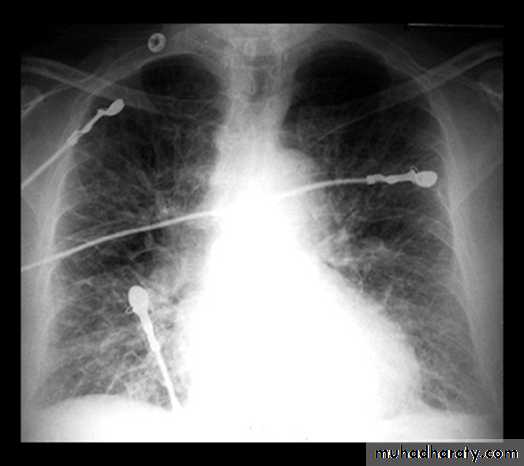

Implantable Cardioverter-Defibrillators for HF( ICD) –CRT

Sustained ventricular tachycardia is associated with sudden cardiac death in HF.

About one-third of mortality in HF is due to sudden cardiac death.Patients with ischemic or nonischemic cardiomyopathy, NYHA class II to III HF, and LVEF ≤ 35% have a significant survival benefit from an implantable cardioverter-defibrillator (ICD) for the primary prevention of SCD.

Cardiac-Resynchronization-Therapy